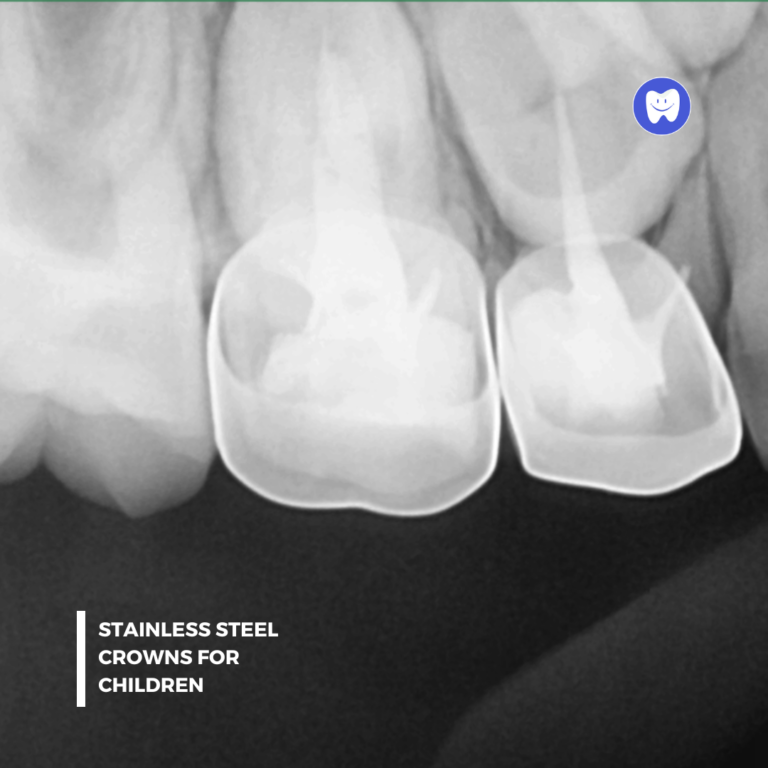

• Thorough examination and digital X-rays to assess the extent of damage.

• Placing a temporary or permanent crown for added protection.